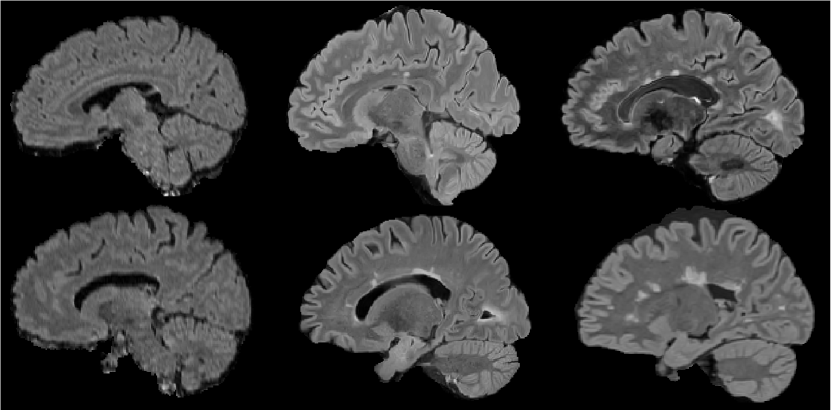

Figure 3 shows examples from the three presented datasets, each image represents a sagittal section of the FLAIR modality in the MNI space after intensity normalization. The two images on the left are examples from the ISBI dataset. We notice blurring effects which makes it hard to distinguish precisely brain structures. This blur comes from 2D low resolution acquisitions. In the middle, the two examples come from the MSSEG’16 dataset. These 3D FLAIR are noticeably of higher resolution than the other images. Therefore, lesion boundaries are more easily delineated and main structures are clearly apparent. The final two images on the right are from our In-house 3D dataset. The 3D resolution enables the differentiation of white matter, gray matter, and shows the lesions clearly.

In terms of FLAIR images, we notice that both MSSEG’16 and In-house dataset (3D FLAIR) propose better visual quality than ISBI dataset (2D FLAIR).